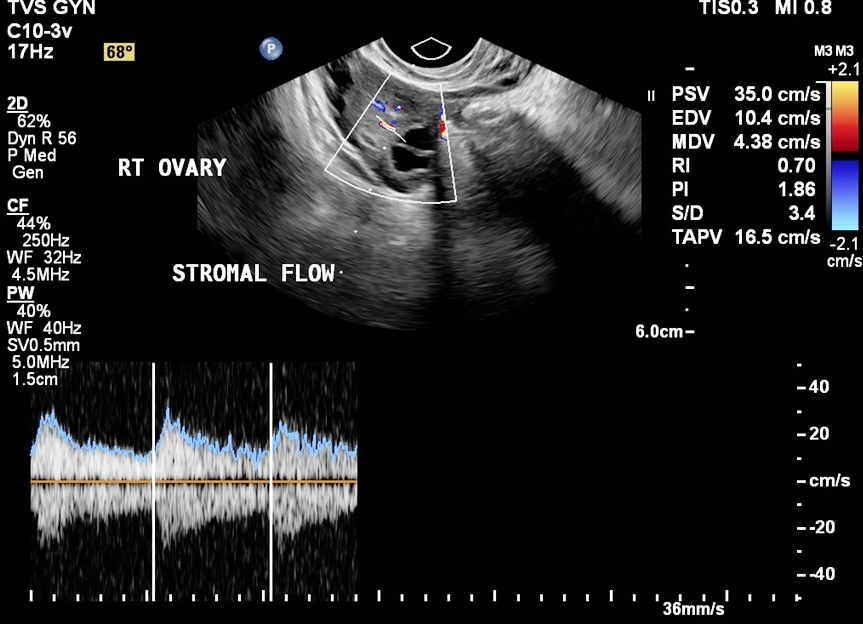

The baseline scan is usually done on the 2nd or 3rd day of the menstrual cycle transvaginally. Several parameters are assesed, including presence of cysts in the ovaries, appearance of ovaries etc. This scan gives an overview to the gynecologist in planning ovulation induction and assessing infertility.